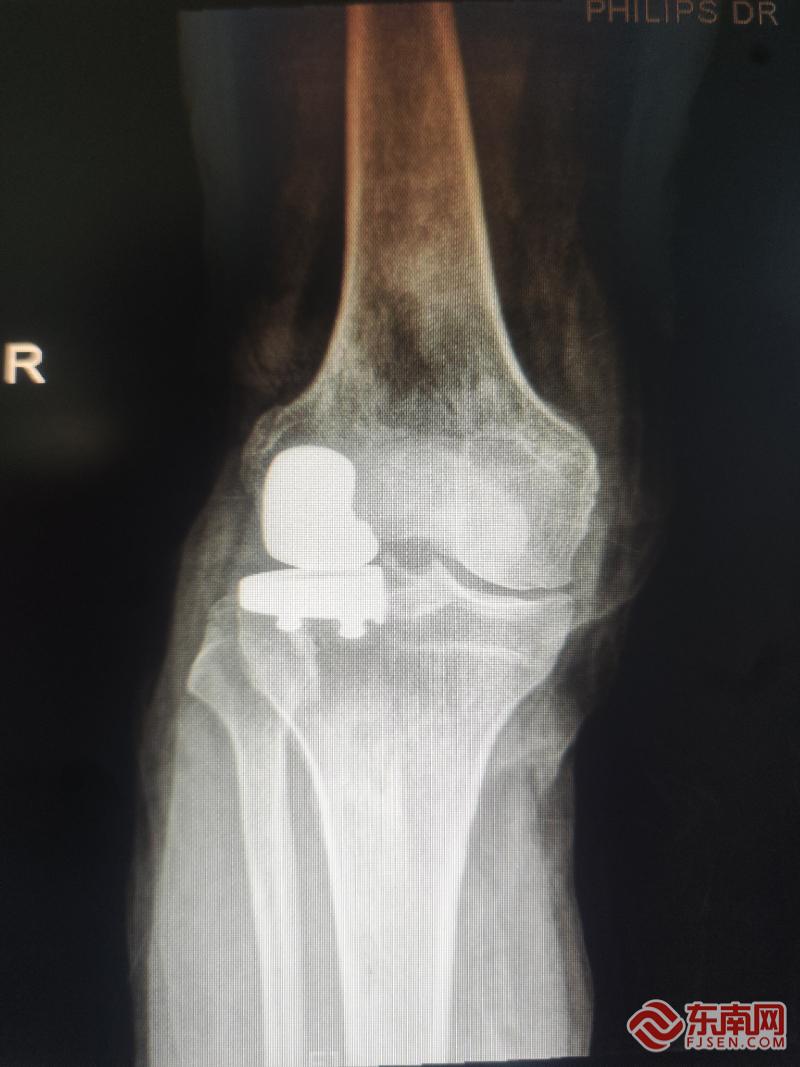

术后片。宁德市中医院供图

据悉,此次手术由孙永强名医工作室核心成员、河南省洛阳正骨医院郑州院区膝关节外三科申晟副主任医师主刀完成。患者常年饱受膝关节骨关节炎困扰,影像学检查显示其病变主要局限于膝关节外侧间室,经孙永强教授团队联合会诊、精细评估与方案规划后,决定采用创伤更小、恢复更快的膝关节外侧单髁置换术,精准破解患者病痛。

“单髁置换术被誉为‘关节置换中的微创手术’,它只置换膝关节中磨损的部分,最大限度地保留了患者自身的交叉韧带及健康的骨质和软骨。”申晟副主任医师介绍,与传统全膝关节置换相比,该手术切口更小、出血更少、术后疼痛感更轻,能帮助患者更快恢复关节功能,早日重返正常生活。